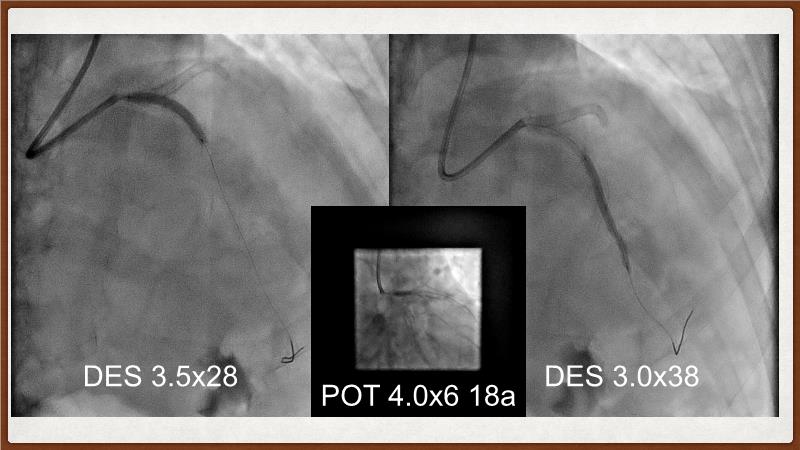

This session explores the challenges of treating calcified lesions during percutaneous coronary intervention (PCI). Learn how calcium can impede stent deliverability and expansion, potentially leading to thrombosis and restenosis. Discover the innovative Shockwave IVL technology, which uses sonic pressure waves to fracture calcium without harming surrounding tissues. The discussion also covers the ongoing challenges of calcified nodules, the importance of intracoronary imaging, and how a layered approach with multiple devices can enhance treatment outcomes. Finally, see how the IVL Shockwave C2+ device facilitates targeted energy delivery for effective PCI.

- To uncover practical tips and techniques for IVL in challenging calcified lesions: diffuse, ostial LAD bifurcations and eccentric/calcified nodules